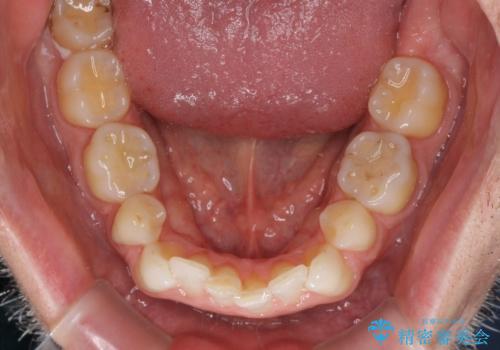

- 上下前歯の叢生を気にして来院された患者様です。

抜歯矯正をした後戻りということで、歯列不正はそれほど大きくなかったため、インビザライン・ライトを用いて矯正治療を行うこととしました。

前歯のデコボコが残っており、シミュレーション通りに動いていない部分がありましたが、再矯正であることやご本人の満足いくところまでデコボコが改善されたとのことで、治療を終了することとしました。